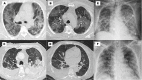

Objectives: Describe the use and findings of cardiopulmonary imaging-chest X-ray (cX-ray), echocardiography (cEcho), chest CT (cCT), lung ultrasound (LUS), and/or cardiac magnetic resonance imaging (cMRI)-in COVID-19 hospitalizations in Latin America (LATAM).

Results: We studied 1,435 hospitalized patients (64% males) with a median age of 58 years classified into three regions: Mexico (Mx), 262; Central America and Caribbean (CAC), 428; and South America (SAm), 745. More frequent comorbidities were overweight/obesity, hypertension, and diabetes. During hospitalization, 58% were admitted to the ICU. The in-hospital mortality was 28%, and it was highest in Mx (37%).The most frequent images performed were cCT (61%), mostly in Mx and SAm, and cX-ray (46%), significant in CAC. The cEcho was carried out in 18%, similarly among regions, and LUS was carried out in 7%, with a higher frequently in Mx. Abnormal findings on the cX-ray were peripheral or basal infiltrates, and in cCT abnormal findings were the ground glass infiltrates, more commonly in Mx. In LUS, interstitial syndrome was the most abnormal finding, predominantly in Mx and CAC.Renal failure was the most prevalent complication (20%), predominant in Mx and SAm. Heart failure developed in 13%, predominant in Mx and CAC. Lung thromboembolism was higher in Mx while myocardial infarction was in CAC.Logistic regression showed associations of abnormal imaging findings and their severity, with comorbidities, complications, and evolution.

Conclusions: The use and findings of cardiopulmonary imaging in LATAM varied between regions and had a great impact on diagnosis and prognosis.